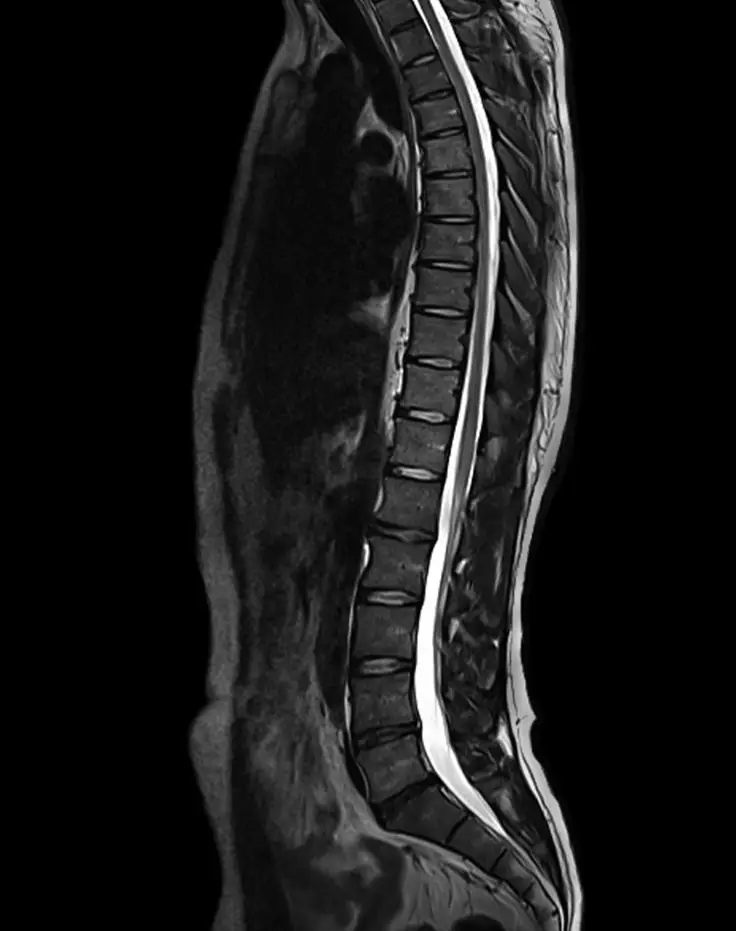

МРТ пояснично-крестцового отдела позвоночника

Визуализация позвонков поясничного и крестцового отделов позвоночника, межпозвонковых дисков, конуса спинного мозга, волокон конского хвоста, спинномозговых корешков, окружающих мягких тканей.